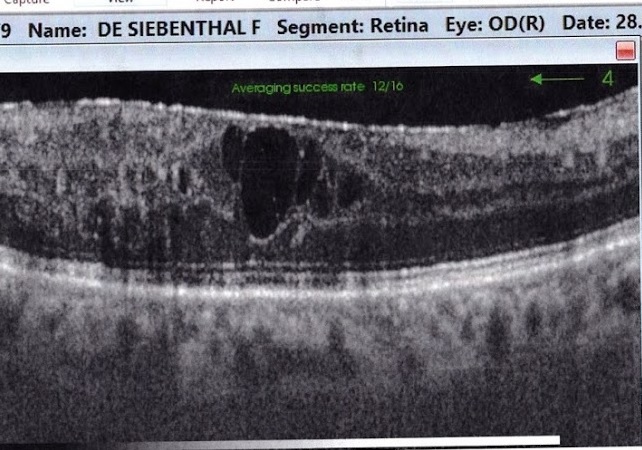

SOS, je perd mes yeux. La surface de la rétine a des pustules pleines d'eau..., surtout l’œil à droite

Suite à mes attaques de l'année dernière ET à MON DIABèTE , mes deux yeux ne sont pas assez oxygénés.

Images des surfaces des deux rétines